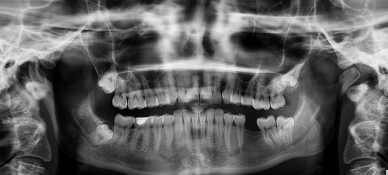

치아의 종류

사람의 치아는 역할에 따라 여러 종류로 나뉩니다:

- 앞니(절치)

- 위치: 입의 앞쪽

- 기능: 음식을 자르고 깨무는 역할

- 송곳니(견치)

- 위치: 앞니 옆

- 기능: 음식물을 찢고 강하게 물어뜯는 역할

- 어금니(구치)

- 위치: 입의 뒤쪽

- 기능: 음식을 갈고 부수는 역할

- 소구치와 대구치로 나뉩니다.

- 사랑니(제3대구치)

- 위치: 어금니의 가장 뒤쪽

- 기능: 현재는 기능이 거의 없으며, 일부 사람에게는 아예 나지 않기도 합니다.